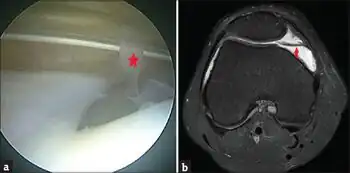

If the plica tethers the patella to the femoral condyle, the symptoms may cause it to be mistaken for chondromalacia patellae. Diagnosis is often complicated by the thin structures of plicae, fenestrated septum or unfenestrated septum all being too fine to resolve well even in MRI.

- ↑ Ravikanth, Reddy; Pilar, Anoop; Majumdar, Pooja (2020). "Magnetic resonance assessment of medial plica syndrome of knee from child to adult with arthroscopic correlation: A single center experience and literature review". Tzu Chi Medical Journal. 32 (4): 351. doi:10.4103/tcmj.tcmj_150_19. Archived from the original on 7 February 2023. Retrieved 6 February 2023.